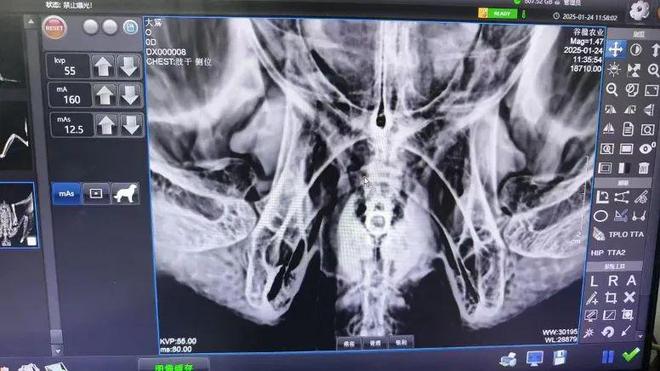

前不久,张先生打来求助电话,称自己捡到一只老鹰,区园林绿化局救助人员立即到达现场,与市民签好“救护单”,将受伤大鵟送往野生动物救助中心。X光扫描排除骨骼损伤,PCR检测筛查禽流感和支原体,救助人员仔细清理羽毛间的苍耳……在确认其符合放归标准后,工作人员为它补充电解质、完成驱虫处理,最终选择适宜生境成功放飞。整个过程严格遵循“接报-登记-初步诊断-系统检查-治疗(死亡的登记后无害化处理)-健康评估-科学放归”的标准化流程,展现出野生动物救护体系的专业厚度。

他们让“稀客”变“常客”(图1)